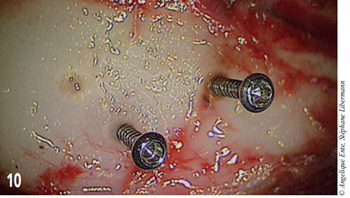

Deux autres vis sont placées dans l’occiput pour permettre la fixation de la prothèse de PMM (figure 10).

Figure 10 – Visualisation de 2 vis occipitales.